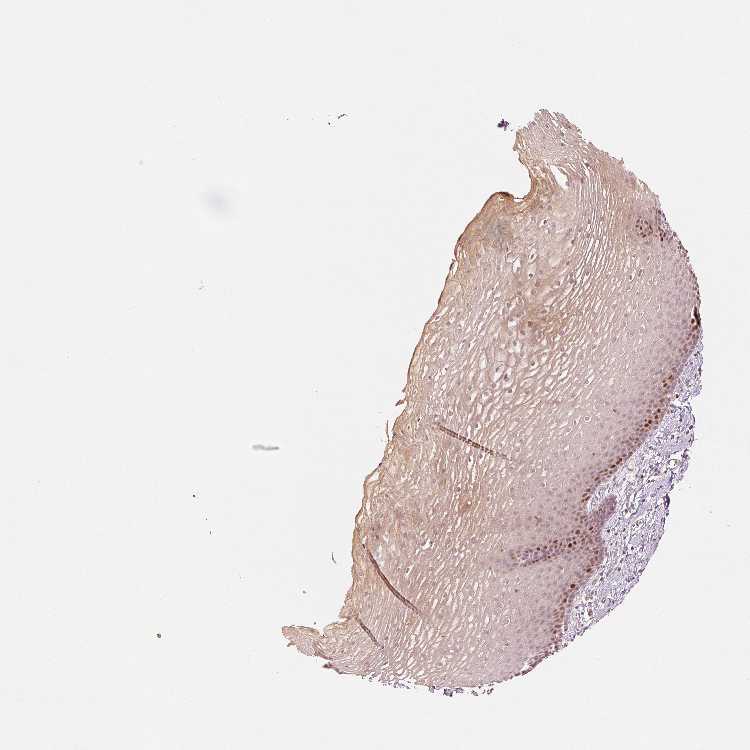

ESOPHAGUS - Antibody stainingi

Antibody staining in the annotated cell types in the current human tissue is reported as not detected, low, medium, or high, based on conventional immunohistochemistry profiling in selected tissues. This score is based on the combination of the staining intensity and fraction of stained cells.

Each image is clickable and will lead to virtual microscopy that enables deeper exploration of all samples and also displays staining intensity scores, fraction scores and subcellular localization as well as patient and tissue information for each sample.

Antibody HPA054060

Squamous epithelial cells Medium